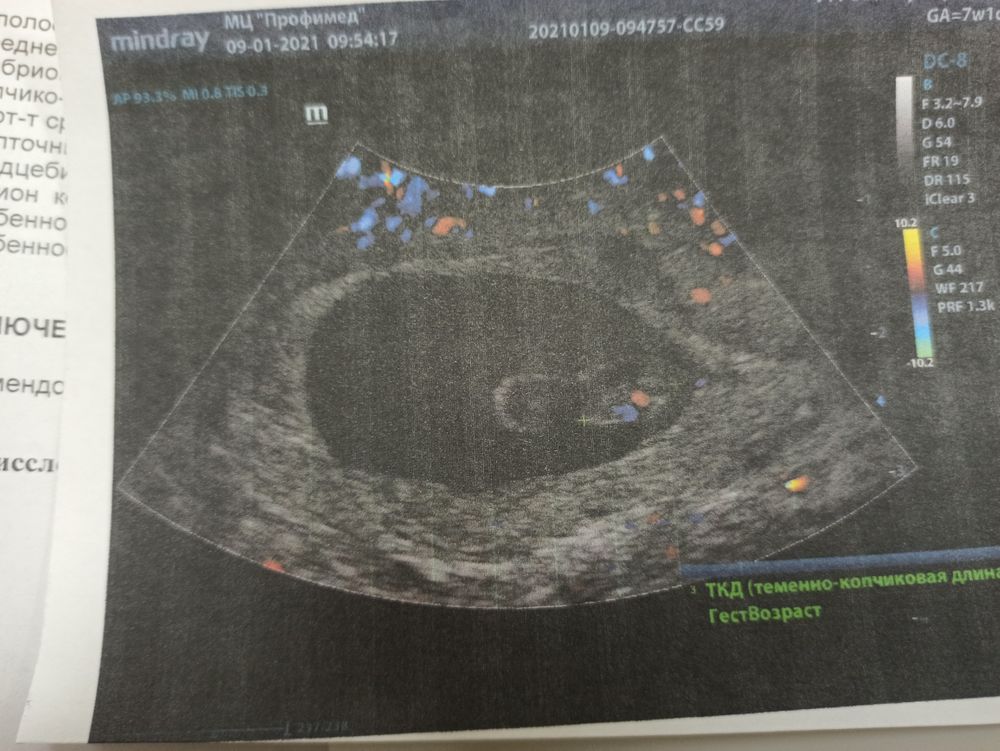

7 недель. Первое УЗИ ❤️

Сегодня было первое УЗИ❤️😍

Я обещала себе не реветь😁 Но узист была такой милой все рассказывала, вот говорит человечек вот сердечко( я стойко держалась😁) и когда она дала послушать ♥️ меня прорвало😁😭. Наша бусинка♥️ немного отстаёт по месячным 7н2д( я считала 1д🤔) по КТР 6н4д. Врач сказал все в норме догонит🤗